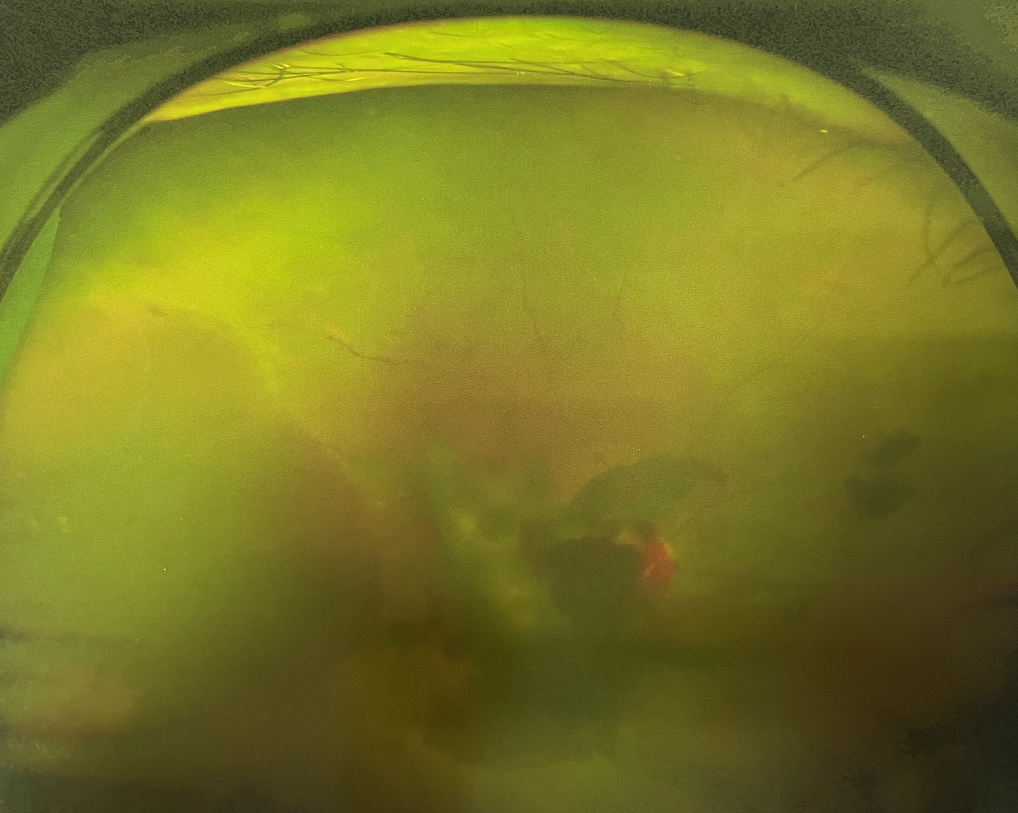

眼底出血多指玻璃體內(nèi),眼睛更深處的視網(wǎng)膜出血。通常情況下,肉眼難以發(fā)現(xiàn)眼底出血,而且發(fā)病初期眼睛也無明顯癥狀,只有借助專業(yè)的眼底檢查儀器才能觀察到異樣。那么眼底出血嚴(yán)重嗎?

眼底出血嚴(yán)重嗎?對于已出現(xiàn)黃斑水腫、視網(wǎng)膜新生血管的患者,根據(jù)眼底血管造影、oct等檢查結(jié)果,給予玻璃體腔注射抗VEGF藥物及激光治療,可以減輕黃斑水腫,使視網(wǎng)膜新生血管消退,以免進(jìn)一步發(fā)生玻璃體出血、視網(wǎng)膜脫離等嚴(yán)重并發(fā)癥的出現(xiàn)。對于玻璃體出血者,傳統(tǒng)認(rèn)為玻璃體出血3-6個月不吸收再進(jìn)行手術(shù)干預(yù),但近年來因為顯微手術(shù)設(shè)備及玻璃體切割技術(shù)已非常成熟,故對于1個月不吸收的玻璃體出血者就可以考慮手術(shù),即手術(shù)時機(jī)應(yīng)該具體情況具體分析,因人而異。